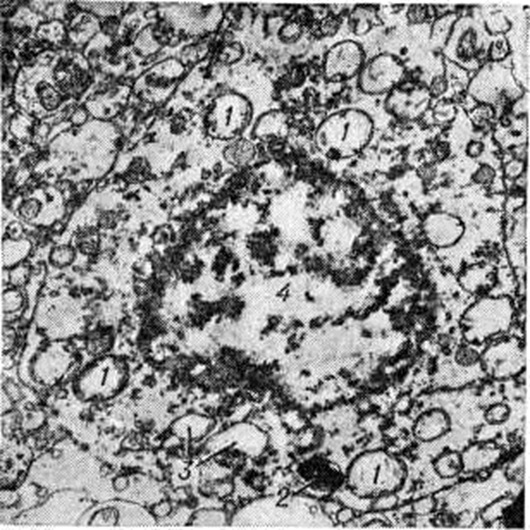

Рис. 2.

Электронограмма нейроцита коры больших полушарий головного мозга с осмиофилией ядра: 1 — изменённые митохондрии; 2 — вакуоли; 3 — тёмные осмиофильные тела, свидетельствующие об аутофагических процессах в клетке вследствие нарушения белкового обмена при гипоксии; 4 — расширенные цистерны гранулярного ретикулума (показатель внутриклеточного отёка при гипоксии); 5 — набухшие отростки астроцитов, окружающие нервную клетку, что указывает на изменение транспорта питательных веществ к клетке и является реакцией глиальной клетки на гипоксию; × 6 300.

В клетках головного мозга обнаруживают вакуолизацию, хроматолиз, гиперхроматоз, кристаллические включения, пикноз, острое набухание, ишемическое и гомогенизирующее состояние нейронов, клетки-тени. При хроматолизе наблюдается резкое уменьшение числа рибосом и элементов гранулярного и агранулярного ретикулума, количество вакуолей увеличивается (рисунок 1). При резком повышении осмиофилии ядра и цитоплазмы митохондрий резко изменяются, появляются многочисленные вакуоли и тёмные осмиофильные тела, цистерны гранулярного ретикулума расширены (рисунок 2).